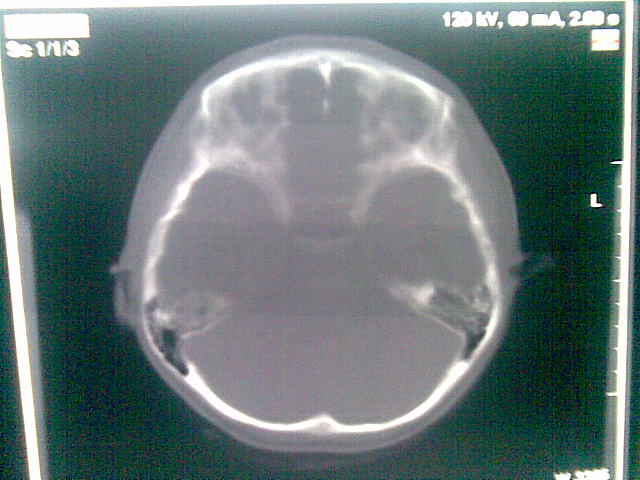

以下是引用随光逐影在2010-1-5 16:32:00的发言:[br]1)鞍上池囊性占位性病变,不排除蛛网膜囊肿可能;建议行mri检查。2)脑积水。

以下是引用yangyang2000在2010-1-5 20:41:00的发言:[br])鞍上池囊性占位性病变,不排除蛛网膜囊肿可能;建议行mri检查。2)脑积水

以下是引用yangyudong333在2010-1-5 21:28:00的发言:[br]1)鞍上池囊性占位性病变,不排除蛛网膜囊肿可能;建议行mri检查。2)脑积水。